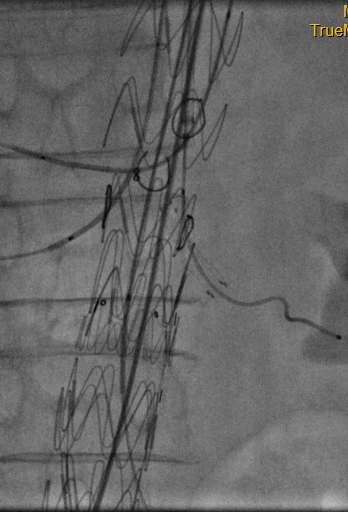

介入开窗手术治疗前后图片对比

手术当天,团队成员分为两组同步开展操作,一组建立手术通路(右腋动脉及右股动脉),一组改装支架,主体支架经右侧股动脉入路,被精准输送至病变部位,部分释放并顺利展开腹腔干、肠系膜上动脉外分支。

手术团队通过导管导丝操作技术,依次对腹腔干、肠系膜上动脉、双肾动脉进行精准选入并植入支架,成功完成对重要内脏分支动脉的血运重建。最后,一枚大动脉覆膜支架被精准植入胸降主动脉,与主体支架完美衔接,将夹层动脉瘤完全隔绝于血液循环之外,彻底消除破裂风险。术后最终造影结果显示:夹层动脉瘤隔绝彻底,无内漏发生,腹腔干、肠系膜上动脉、双肾动脉等四支血管血流通畅。